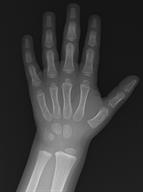

An X-ray showing the lower arm, wrist, and hand.